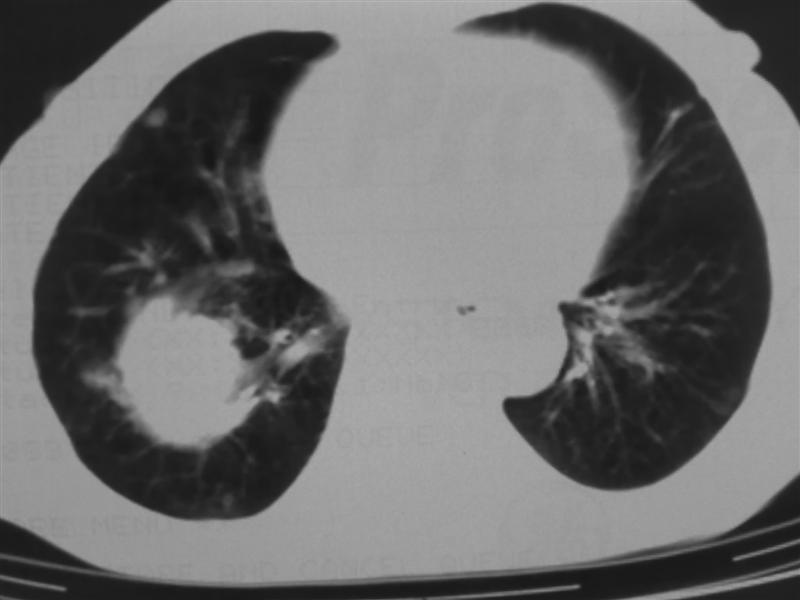

标题: CT10080:F76Y,各位老师发表高见!!! [打印本页]

标题: CT10080:F76Y,各位老师发表高见!!!

右下肺周围型肺癌伴双肺右侧叶间 胸膜及右肺门淋巴结转移